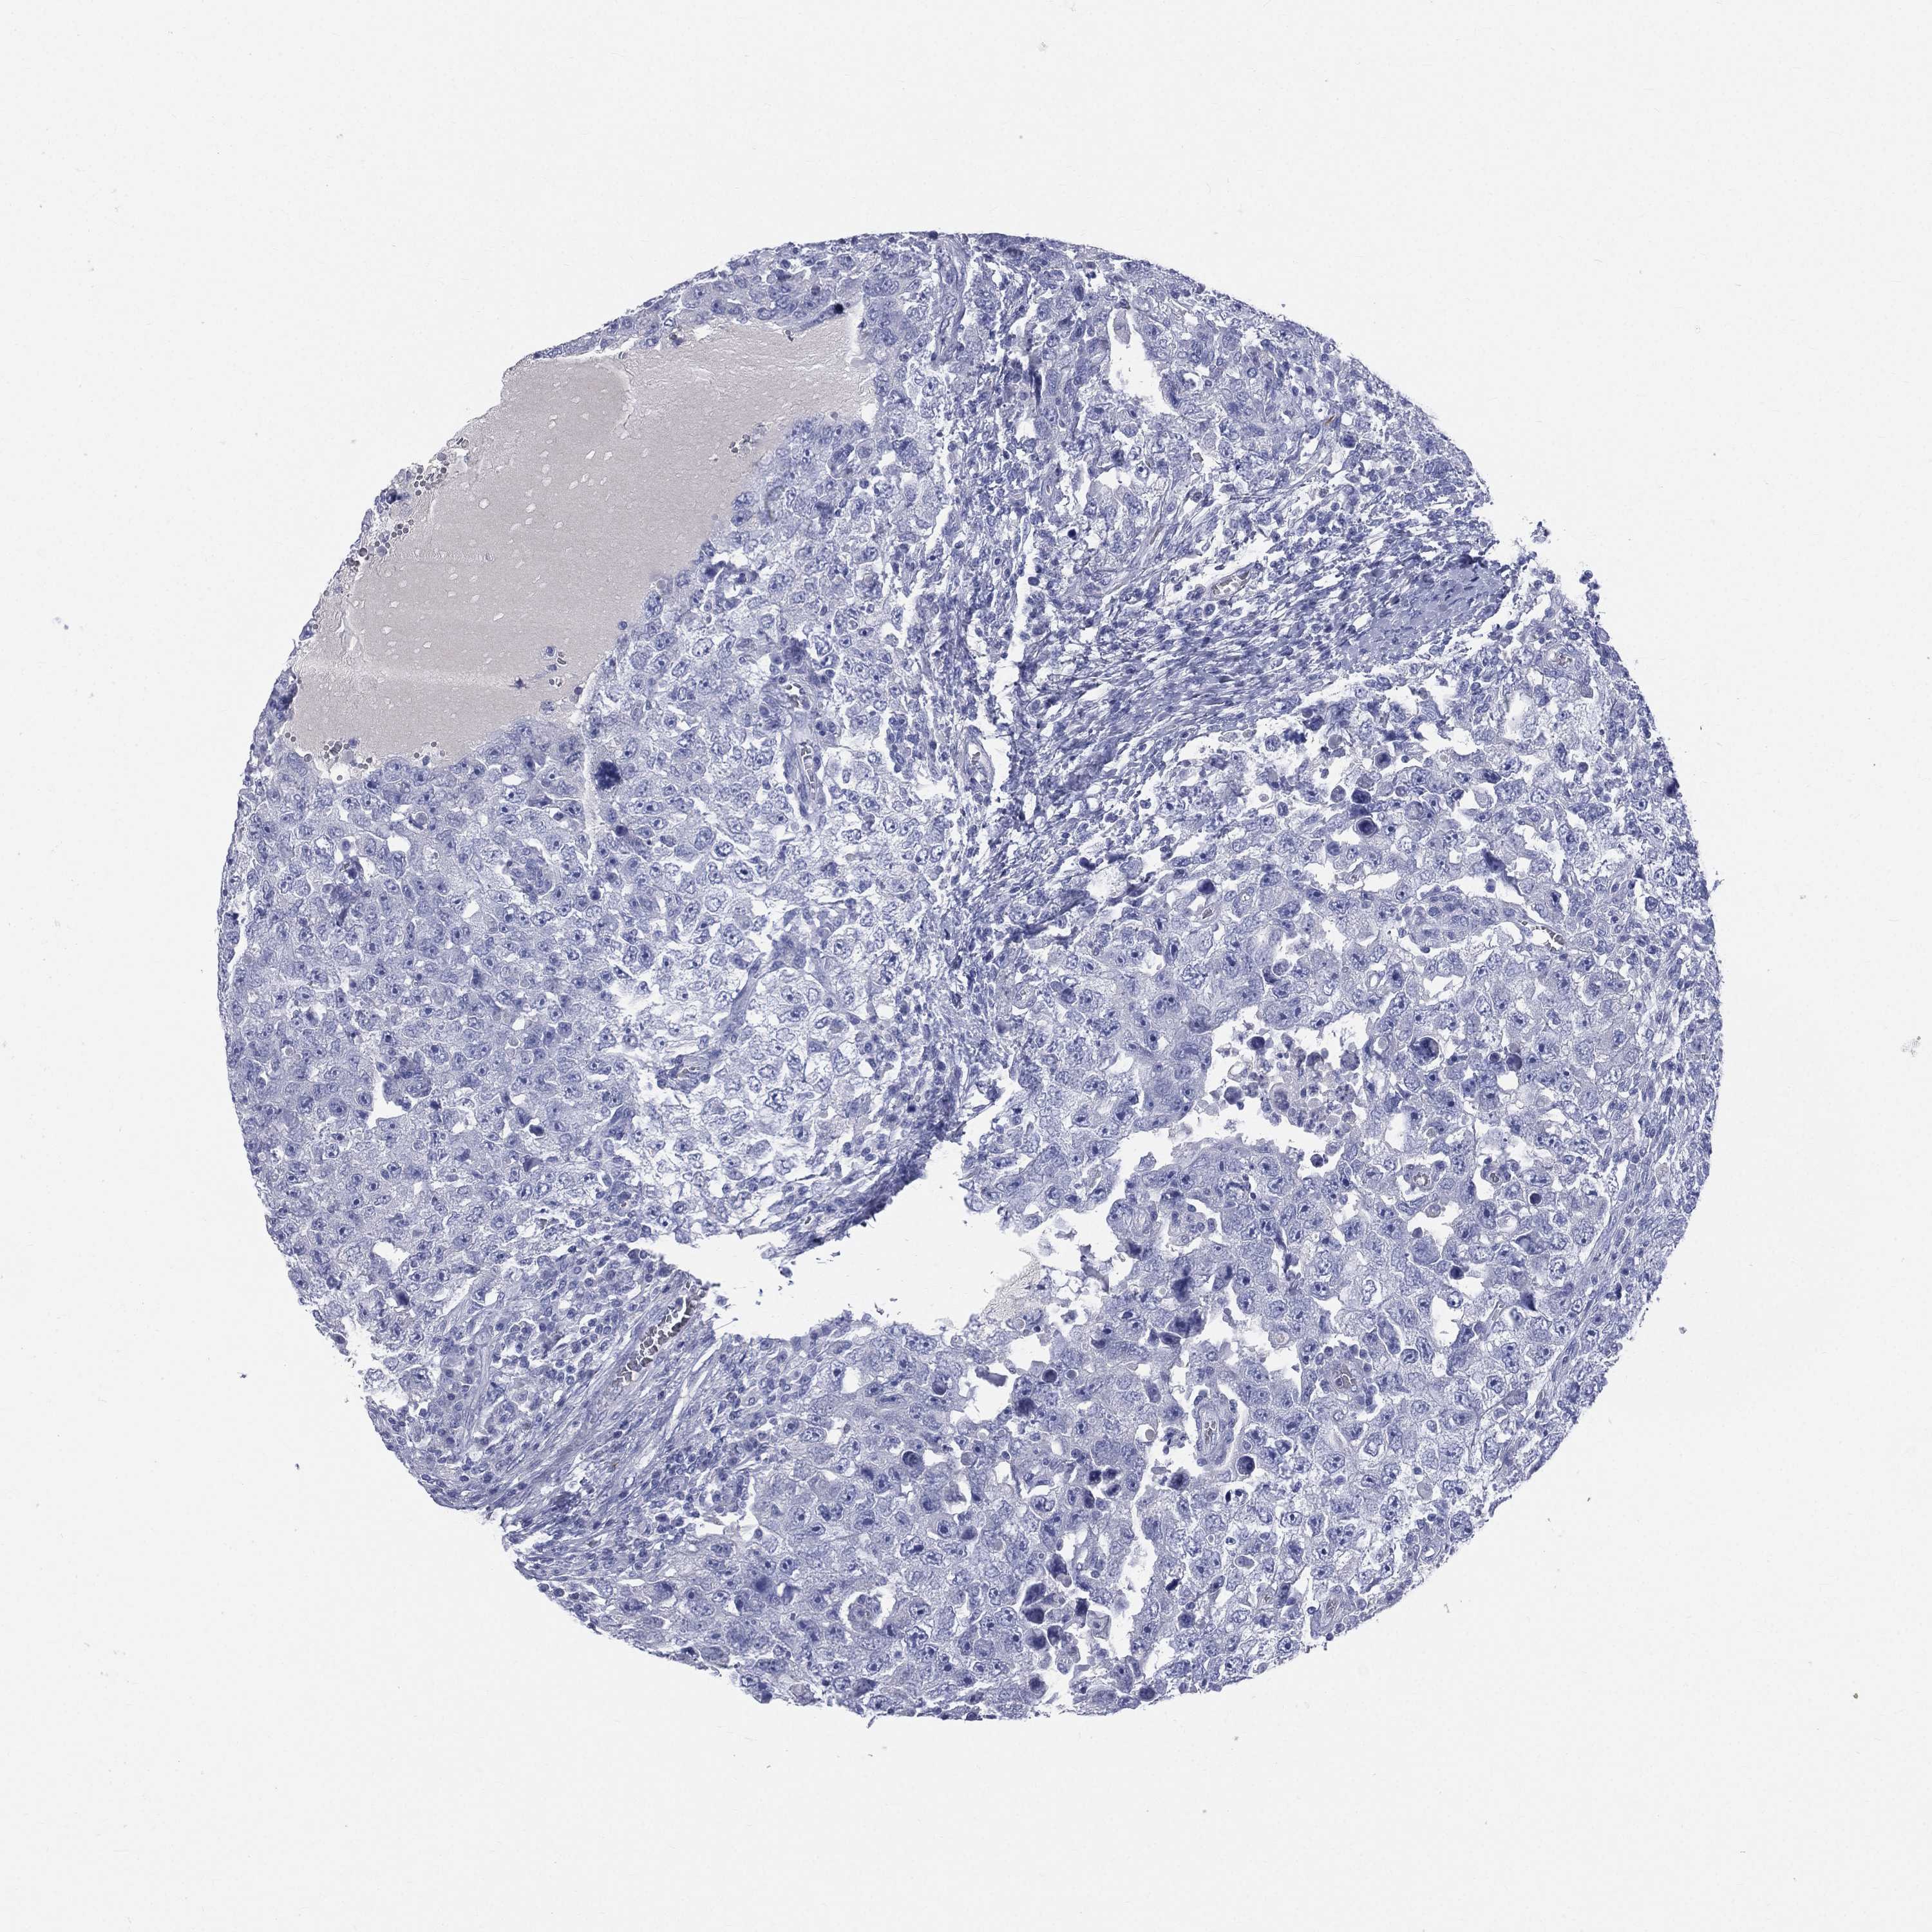

TESTIS CANCER - Protein expressioni

A mouse-over function shows sample information and annotation data. Click on an image to view it in a full screen mode. Samples can be filtered based on level of antibody staining by selecting one or several of the following categories: high, medium, low and not detected. The assay and annotation is described here.

Note that samples used for immunohistochemistry by the Human Protein Atlas do not correspond to samples in the TCGA dataset.

Antibody stainingi

Antibody staining in the annotated cell types in the current human tissue is reported as not detected, low, medium, or high, based on conventional immunohistochemistry profiling in selected tissues. This score is based on the combination of the staining intensity and fraction of stained cells.

Each image is clickable and will lead to virtual microscopy that enables deeper exploration of all samples and also displays staining intensity scores, fraction scores and subcellular localization as well as patient and tissue information for each sample.

Antibody HPA047750

Antibody HPA066795

Antibody CAB003787

Staining

High

Medium

Low

Not detected

Intensity

Strong

Moderate

Weak

Negative

Quantity

>75%

75%-25%

<25%

None

Location

Nuclear

Cytoplasmic/membranous

Cytoplasmic/membranous,nuclear

Seminoma, NOS

Carcinoma, Embryonal, NOS